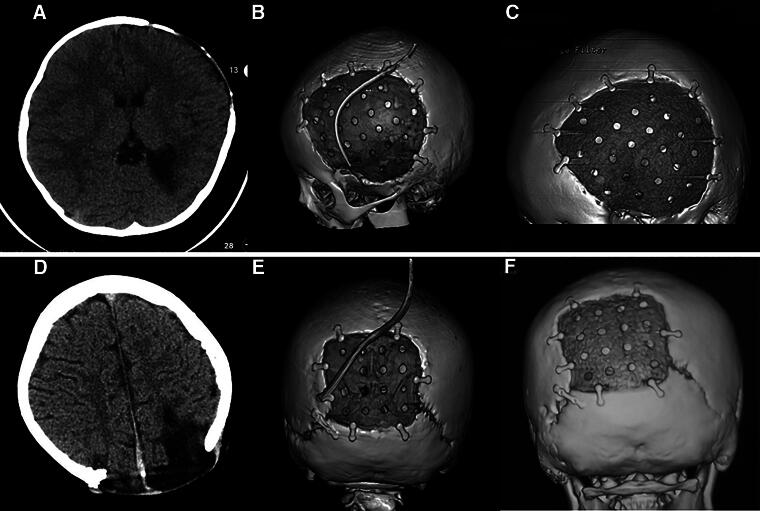

This study aimed to explore the experience and complications of cranioplasty (CP) with polyether ether ketone (PEEK) in pediatric and adolescent patients after decompressive craniectomy (DC). A total of 62 children (aged <18 years) with cranial bone defects due to DC underwent CP with a custom-made PEEK at our department between January 2018 and April 2023. The clinical characteristics, radiological features, surgical conditions, postoperative complications, and follow-up results of these patients were analyzed retrospectively. Kaplan-Meier survival analysis and Cox regression were used to analyze data. The age of the patients ranged from 2 to 17 years. The follow-up periods ranged from 12 to 70 months. Six patients experienced subcutaneous fluid accumulation (9.7%), five experienced epidural fluid accumulation (8.1%), and two experienced scalp inflammation (3.2%), which all were cured before discharge. Seven patients experienced bone gap expansion at the interface between the cranial bone and PEEK during follow-up (11.3%). Univariate analysis showed that DC-CP time interval (<3 months) and age were two influencing factors. Multivariate analysis revealed that age was the most important factor (p < 0.005, hazard ratio = 0.250, 95% confidence interval: 0.096-0.652). No reoperation was performed. Medical follow-ups were carried out further. For pediatric patients with cranial defects after DC who receive CP with a custom-made PEEK, two variables including younger age and too short DC-CP time interval may be unfavorable factors, to make patients experience bone gap expansion at the interface between the cranial bone and the PEEK. Additional data should be collected to validate our conclusions.